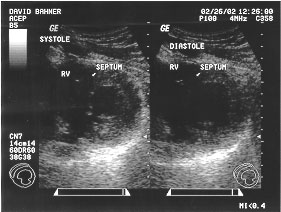

Cardiac cycle - short axis (labeled)